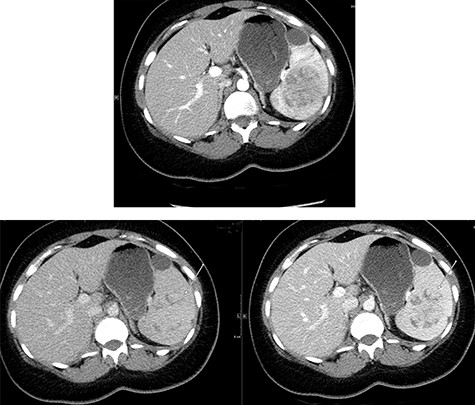

A repeat contrast-enhanced CT scan 21 months later showed an increase in size of the lesion to 8.0 × 7.2 × 6.6 cm (Fig. 4). Positron emission tomography (PET) CT demonstrated the mass to be moderately hypermetabolic with a standardized uptake value (SUV) of 4.7 (Fig. 5).

The post-contrast CT axial image showing central hypodense splenic lesion in portovenous phase (arrow—right image) which becomes isodense on delayed images (arrow—left image).